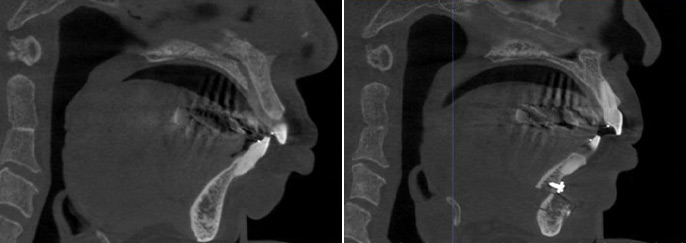

정상 기도

충분한 공간

좁아진 기도

턱 후퇴 시

김찬우 원장이 직접

CT 기반 구조 분석으로

턱 위치와 숨길 상태를 함께 확인합니다.

턱 위치

숨길(기도) 공간